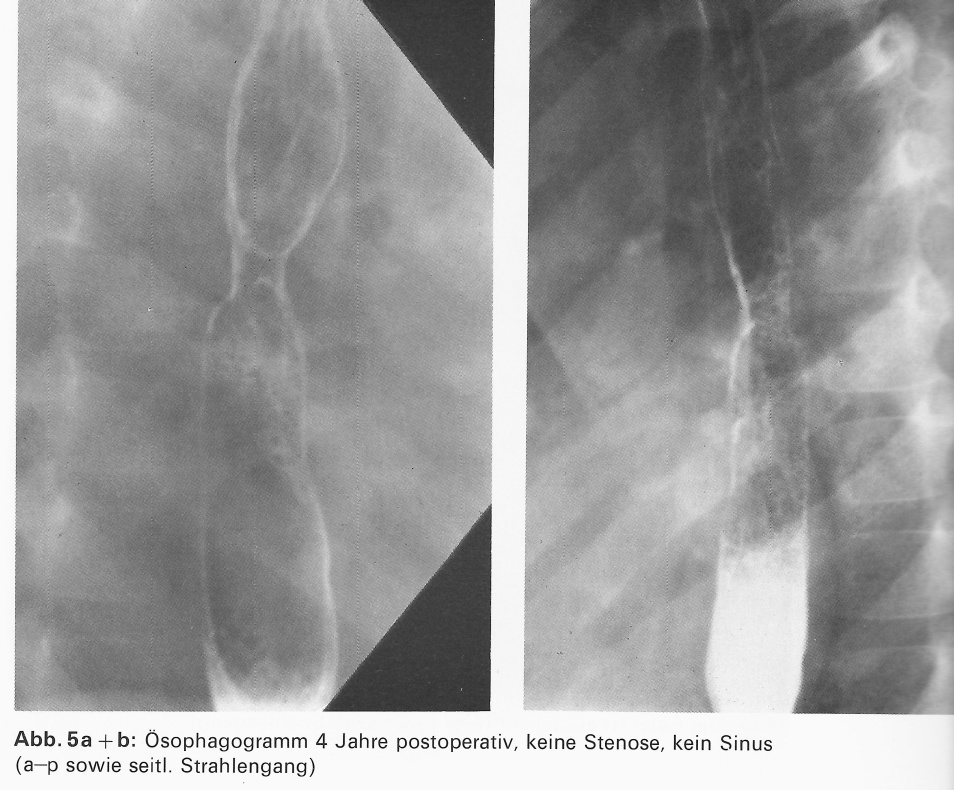

Ishida-Saitama/Japan, Kontor-Budapest u. weiteren) wurden die gesammelten Erfahrungen anhand von Langzeitergebnissen diskutiert. Ein ausgiebig besprochenes Thema war die Bougierungsbehandlung der Ösophagussegmente bei Atresie Typ II n. Vogt.

Unabhängig von Hays et al.*8 und Howard u. Myers*10 war von Haße*6 eine eigene Bougierungsmethode entwickelt worden. Seit 1967 wurden bei 5 Neugeborenen mit einer Typ II Ösophagusatresie nach Vogt beide Segmente –gastrales via Gastrostomie – bougiert,bis sie sich ohne Druck um 1-2 cm überlappten.

Als Spätkomplikation trat bei diesem inzwischen 36 jährigen Pat. eine Ösophago-broncho-pulmonale Spätfistel. Diese wurde in der Chirurgischen Universitätsklinik Hamburg-Eppendorf 2001 operativ geschlossen.

| Abb. 21: Ösophagogramm 4 Jahre nach der Operation. Keine Stenose, keine Fistel |

Booß*2 berichtete auf dem 2. Berliner Symposium 1990 über 17 Kinder, die in Bremen, Mainz und Berlin-Wedding nach dieser Methode behandelt worden sind. Trotz des Auftretens eines korrigierbaren Refluxes bei 7 Kindern hielt er, ebenso wie wir, diese Therapie für die Methode der Wahl.